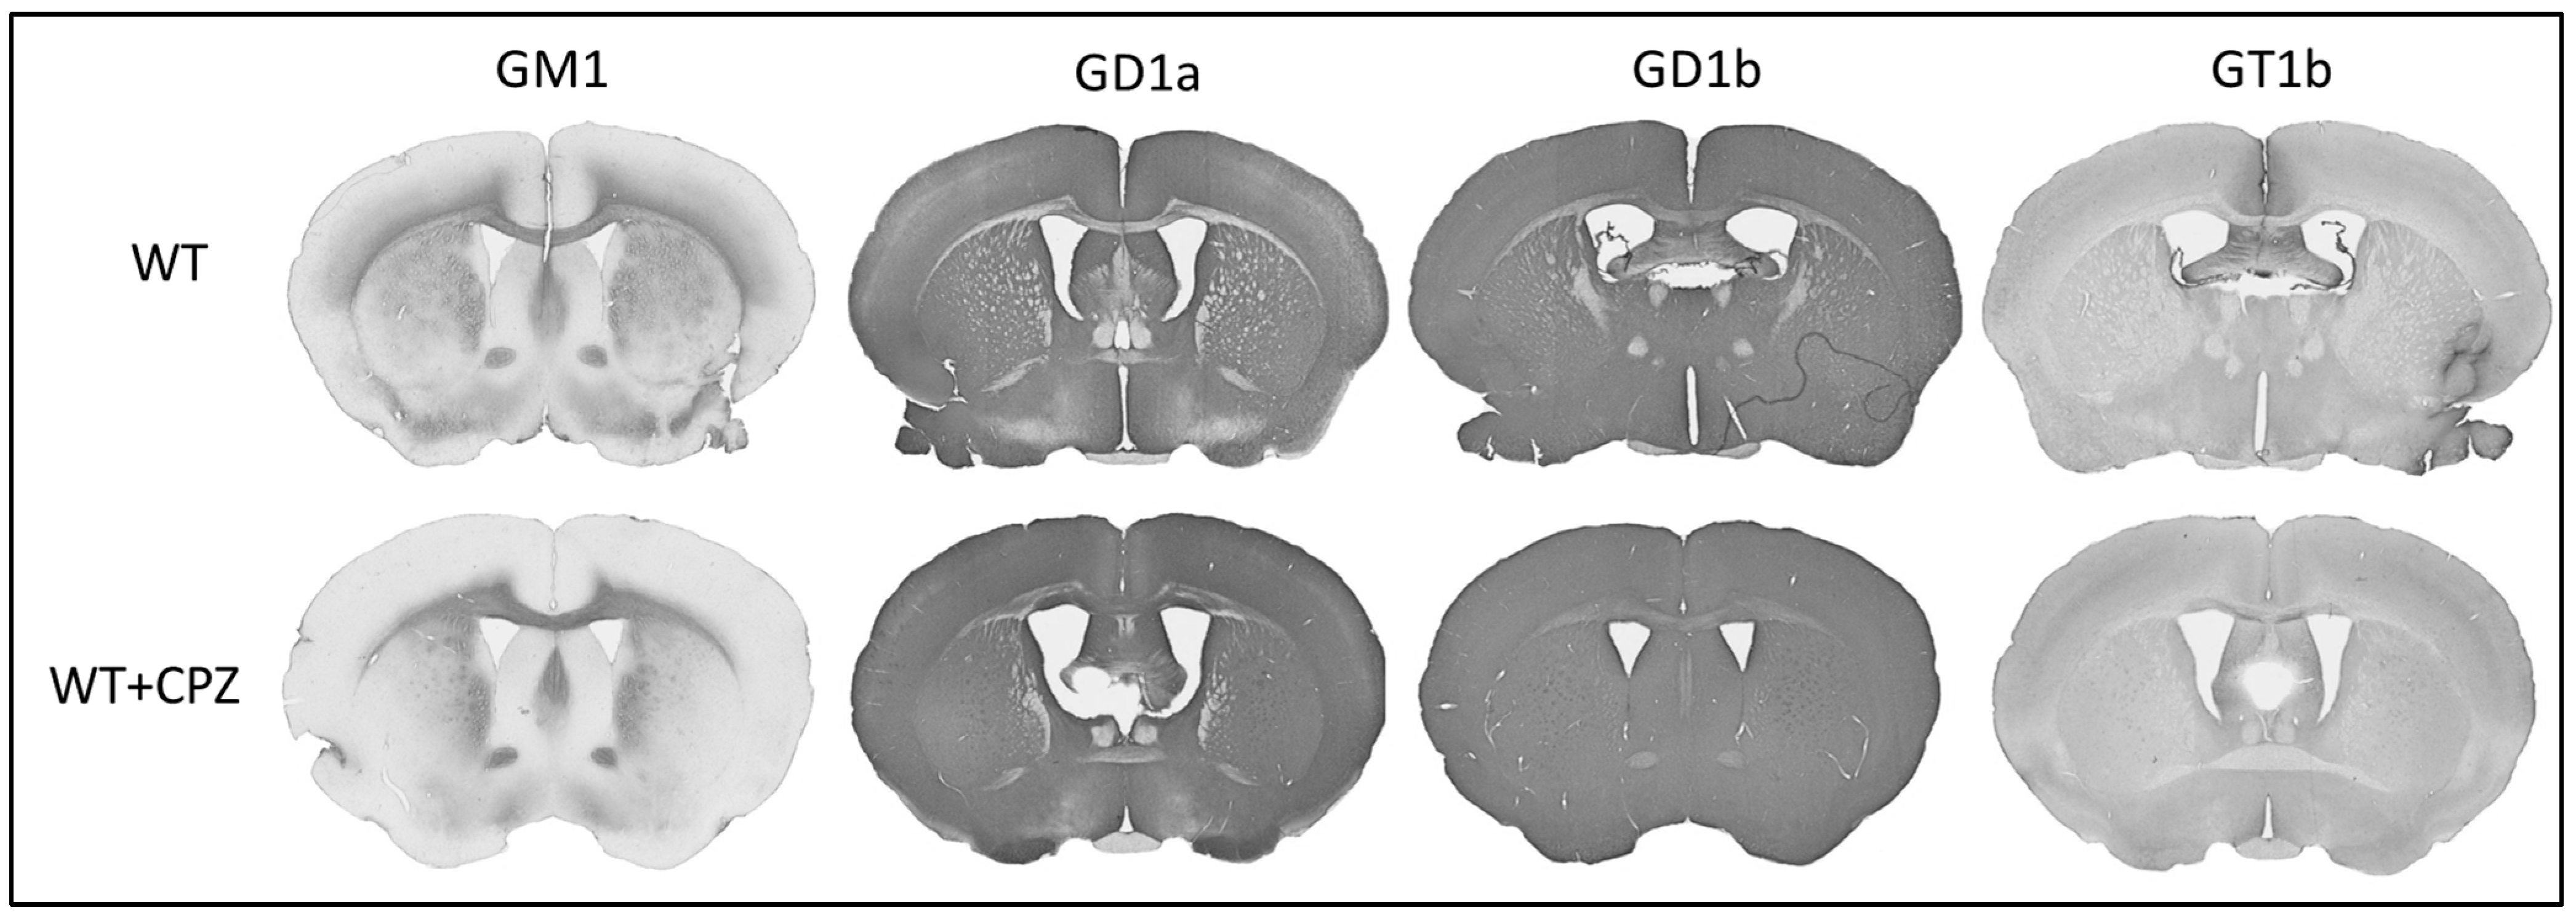

In addition to assessing the extent of demyelination by cuprizone treatment, we also investigated whether this treatment altered the distribution of gangliosides. Figure 6 shows the immunohistochemistry of coronal sections of forebrain from WT mice and WT + CPZ mice labeled with antibodies against the four most abundant brain gangliosides (GM1, GD1a, GD1b and GT1b), which are not present in KO mice. The overall distribution for all four antibodies is virtually identical in the forebrain (Figure 6). However, when we analyzed the corpus callosum, the quantification results showed a significant increase in three (GM1, GD1a and GT1b) of the four complex gangliosides (p < 0.01). Only ganglioside GD1b was not increased in WT + CPZ animals compared with WT animals (Figure 7).

The composition of lipid rafts somehow plays a role in these molecular differences. This is particularly pronounced in B4galnt1-null mice, as they do not synthesize complex gangliosides that are critical for lipid raft integrity and functionality. As integral components of lipid rafts that are essential for the formation of nodes of Ranvier, gangliosides play a critical role in the propagation of the action potential along the myelinated axons [40]. The gangliosides GM1 and GD1a, which are abundant in the nodes of Ranvier and paranodal regions, stabilize the node structure and cluster the ion channels [41]. Early studies using ganglioside-binding ligands showed the localization of GM1 at the nodal axolemma and at the membranes of Schwann cells [42]. Subsequent immunohistochemical studies confirmed the presence of gangliosides such as GM1, GD1a and GQ1b at the nodal gap and paranodal structures [40]. This localization is important because anti-ganglioside antibody-mediated injury to the node can lead to paralytic features of autoimmune neuropathies [43]. In B4galnt1-null mice, disruption of ganglioside synthesis likely alters the organization and function of nodes of Ranvier and impairs neuronal signaling [15,40]. The reduction or absence of specific gangliosides in these mice impairs the integrity of the nodes, resulting in reduced nerve conduction velocity and increased susceptibility to demyelination [41]. Further studies should investigate the mechanisms of changes in ganglioside distribution and their effects on lipid raft functionality in order to better understand the mechanisms of demyelination and improve treatment strategies. We also investigated whether treatment with cuprizone affects ganglioside distribution. Quantitative analysis of the corpus callosum revealed a significant increase in GM1, GD1a and GT1b expression in cuprizone-treated mice, suggesting that cuprizone alters ganglioside composition or access for antibodies. This probably affects the composition of lipid rafts. However, this should be confirmed at the level of lipid rafts, for example, by using super-resolution microscopy.

Figure 6. Immunohistochemical staining of the four major brain gangliosides (GM1, GD1a, GD1b and GT1b) in the brains of wild-type (WT) and cuprizone-treated wild-type (WT + CPZ) mice on coronal sections of the forebrain.